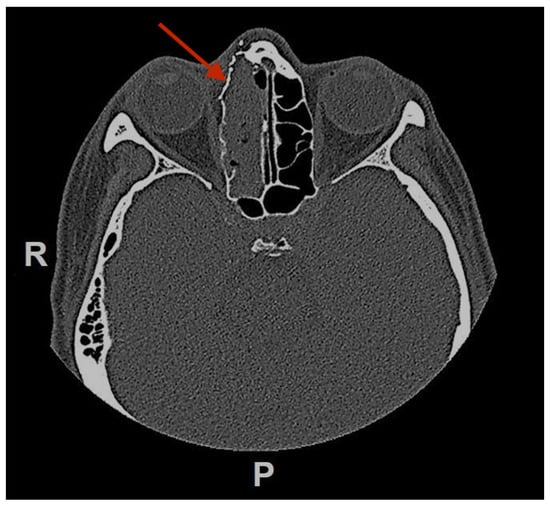

Figure 1.

(A) Preoperative MRI (Time Of Flight TOF sequence in axial view; black asterisk) and CT-scan (B) (axial view; white asterisk) (C) (coronal view; white asterisk), (D) (sagittal view; white asterisk) showing an anterior ethmoidal high vascularized tumor invading the right nasal bone and the medial wall of the right orbit. R = right, P = posterior.